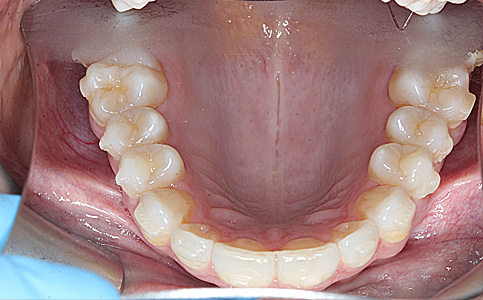

Pacjent zgłosił się do naszego Centrum stomatologii i Ortodoncji FRESHmed w Katowicach w celu poprawnia estetyki swojego uśmiechu. Po konsultacji i dokładnej diagnostyce, usunięto zęby dolne z powodu duzej ruchomości. Zęby zostały zastąpione 6 implantami zębowymi, na których odbudowano cały łuk zębowy dolny metodą All-on-6. Poprawę kształtu i koloru zębów górnych uzyskano poprzez zacementowanie koron pełnoceramicznych.

Zobacz efekty przeciągając suwak w prawo lub w lewo.